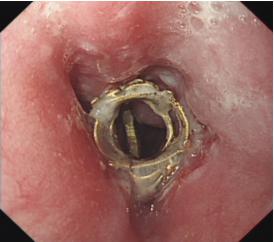

4. 食管、結(jié)腸支架置放:食道癌、結(jié)腸癌晚期失去手術(shù)機(jī)會(huì)或有手術(shù)禁忌癥者,食管氣管瘺等;

幽門惡性梗阻金屬支架置放